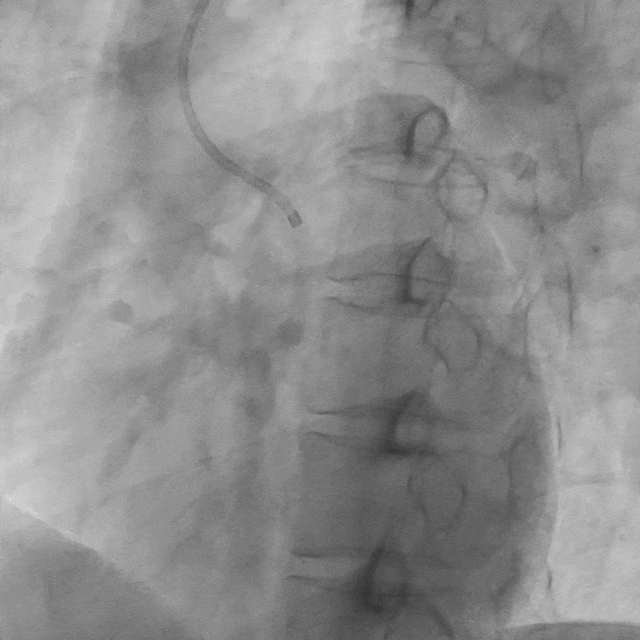

影像素材 | 患者冠状动脉造影 3:右冠起源于左冠窦,较细小,开口及近段狭窄不明显,血流 TIMI3 级